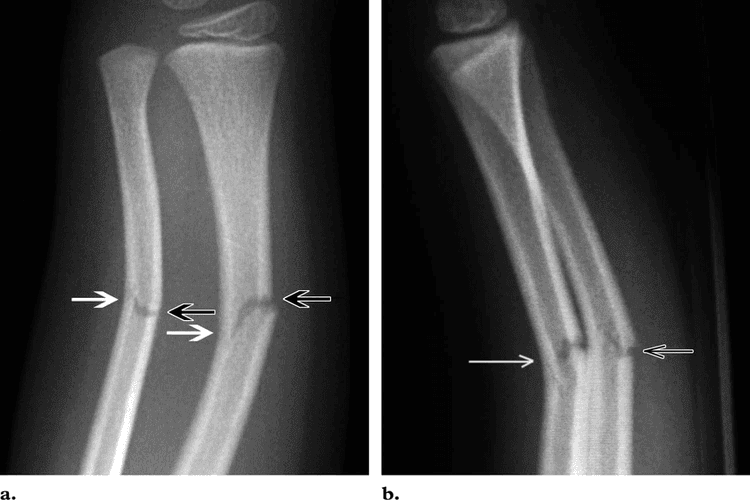

Greenstick Fracture - एका बाजूने फ्रॅक्चर, पण हाड वाकल्याने ते पूर्ण न तुटणे. हे फ्रॅक्चर लहान मुलांमध्ये जास्त आढळून येते कारण त्यांची हाडे लवचिक असतात.